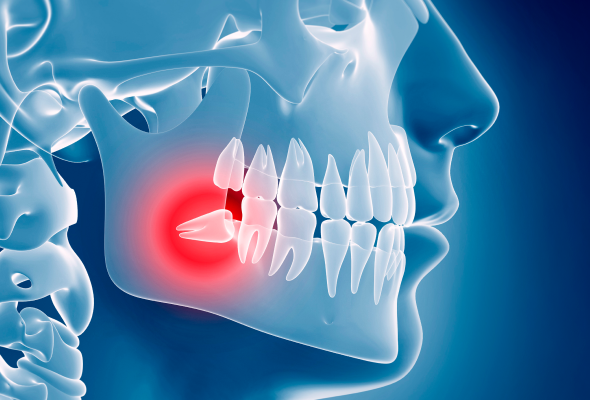

사랑니 발치 과정

사랑니 발치는 사랑니의 위치와 매복 정도에 따라 치료 방법과 난이도가 달라질 수 있습니다.

국소 마취 후 통증을 최소화한 상태에서 진행합니다.

필요 시 최소한의 잇몸 절개를 시행합니다.

절개선을 따라 사랑니를 분리하거나 제거합니다.

발치 부위에 염증 조직이 있는 경우 함께 제거합니다.